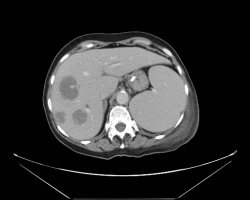

Les syndromes occlusifs, définis par l’arrêt complet du transit intestinal, regroupent quatre signes cliniques élémentaires : l’arrêt des matières et des gaz, les vomissements, la douleur et le météorisme abdominal, d’expression variable selon l’étiologie. […]